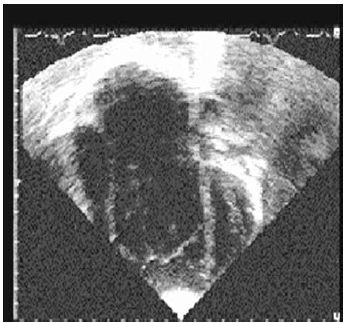

Observe a cardiopatia ilustrada a seguir.

Com base na imagem, pode-se afirmar que